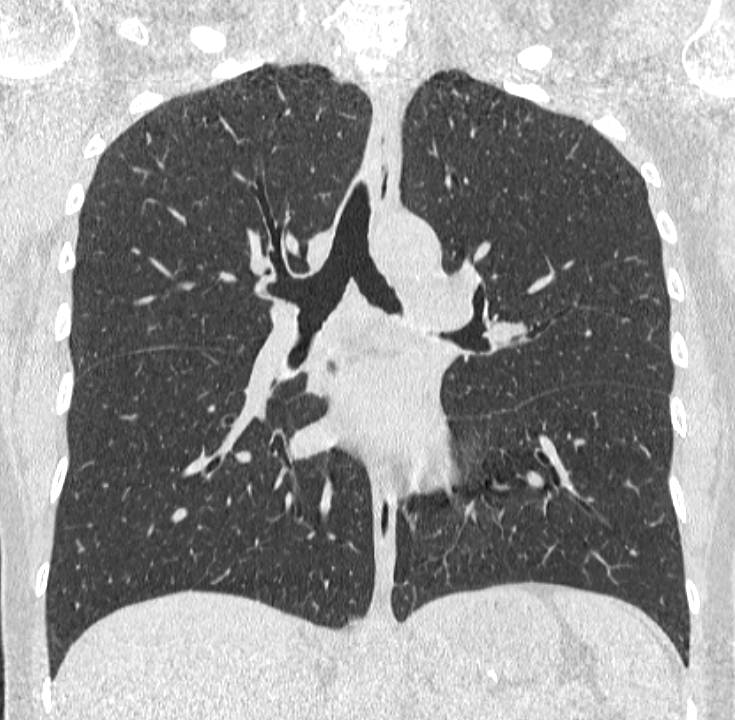

Компьютерная томография бронхов представляет собой виртуальную бронхоскопию, которая позволяет получить точную и достоверную информацию о состоянии трахеи, бронхов, а также оценить структуру легочной ткани, кровеносных сосудов, органов средостения. При обычной бронхоскопии эндоскопический зонд вводится внутрь через дыхательные пути и производится осмотр слизистой трахеи и бронхов, поэтому процедура относится к инвазивным и часто проводится под наркозом.

На основе данных, полученных при сканировании, аппарат создает наглядную 3D модель бронхиального дерева с высочайшей точностью и достоверностью, которая позволяет просматривать интересующие анатомические структуры в разных плоскостях. Метод обладает высокой точностью и дает возможность исследовать мелкие бронхи и бронхиолы, которые из-за узкого просвета бывает невозможно осмотреть при помощи эндоскопической бронхоскопии (возможности метода ограничены размером зонда).

С помощью виртуальной бронхоскопии можно выявить объемные образования в трахее, бронхах, определить степень сужения просвета дыхательных путей. Кроме того, компьютерная томография позволяет оценить состояние окружающих тканей, выявить прорастание опухоли в близлежащие органы, обнаружить метастазирование в регионарные лимфоузлы и ткань легкого.

КТ бронхов помогает диагностировать воспалительные заболевания бронхов и легких, бронхоэктатическую болезнь, инфекционные заболевания, травматические повреждения грудной клетки, аномалии развития.